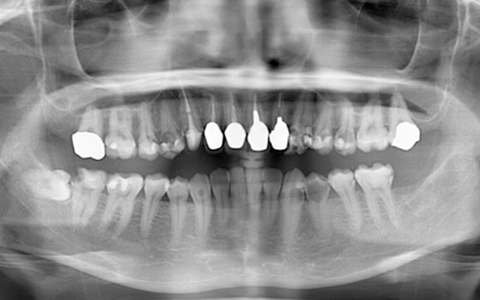

治療前

黄色い矢印の歯が治療前の対象歯です。レントゲンで観察すると、歯の根のお薬が充分には入っていないようです。

麻酔をして歯の中をマイクロスコープで観察すると、元々あった3つの根だけでなく「もう一つの4番目の根」があったのです。根管治療自体は容易に行えましたが、歯の中を明るく拡大できるマイクロスコープを持っていない歯医者さんでは見つけるのが困難だと思われます。この4つ目の歯の根を治療することにより痛みは消失し「抜歯してインプラント」になるという悪循環に陥らず済みました。根管治療はマイクロスコープを使って精密に、また丁寧に行えば歯を長く保たせることができる治療です。やはり神経自体を残すという選択が、歯の保存にとって一番良いということは間違いありません。

| 費用 | デンタルドック:55,000円 根管治療(奥歯):176,000円 MTAセメント:33,000円 歯の土台:33,000円 合計:297,000円 |

| リスク・副作用 | 治療中に一時的な咬合痛や冷温水痛、若干の歯肉の腫れ、発赤などを生じることがあります。また仮歯の時期には仮歯の脱離や破損の可能性、舌感などに違和感を覚えることがありますが、本歯に移行するまでに通常消失します。 ※すべて症例による違いや個人差があります。 |

※表示金額は全て税込みです。